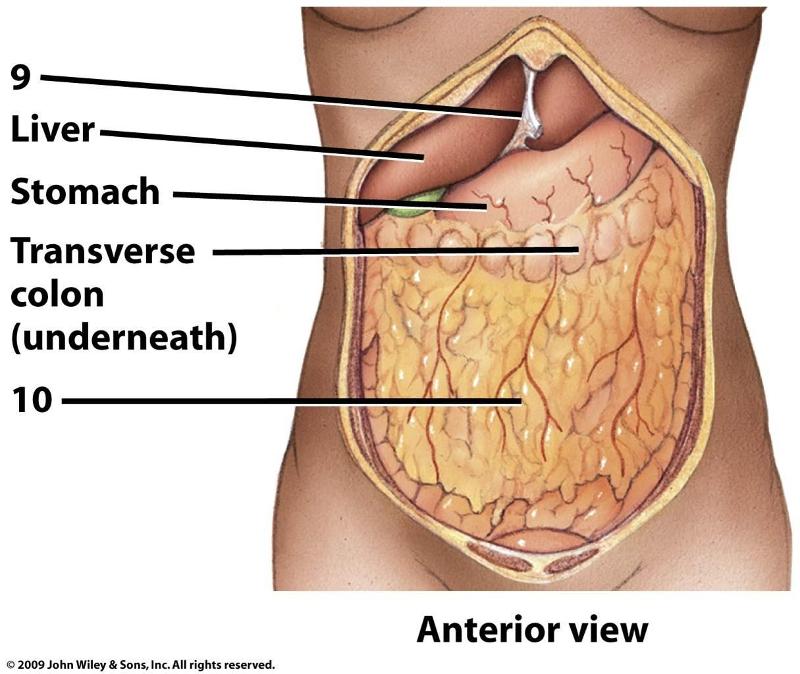

9

9

10

Great omentum

7 & 18

Liver

Stomach